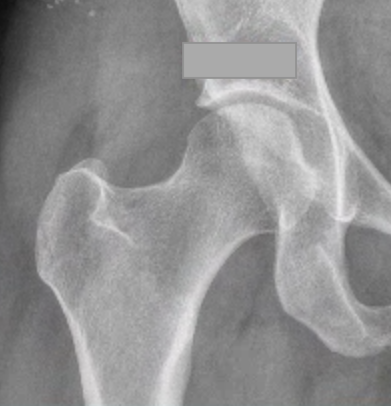

Pincer

Focal pincer

Os acetabuli